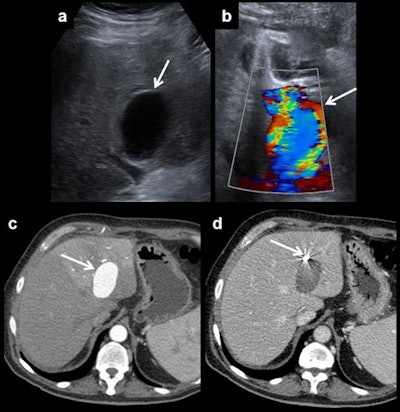

The main imaging findings in patients after liver transplantation are hepatic artery complications (such as thrombosis, stenosis of the anastomosis, and pseudoaneurysms), portal vein abnormalities (such as occlusion and stenosis), and hepatic veins and/or inferior vena cava flow changes (Budd-Chiari syndrome).

Usual post-transplantation findings include right-sided pleural effusion, ascites, perihepatic hematoma, and periportal edema. All of them should resolve in the first weeks after surgery.

"Stenosis may progress to thrombosis. So, stenosis and thrombosis are two entities of the same spectrum of vascular complications of liver transplantation," the authors wrote. "Stenosis can lead to splenic steal artery syndrome. It usually occurs in the first three months, but this time shows differences between patients, describing cases that happen even several years after surgery. Doppler ultrasound is the most useful technique to show this complication, as explained for thrombosis."

In the first three days after liver transplantation, an increased resistance index of the hepatic artery (greater than 0.8) is found in approximately 50% of the patients, they pointed out. If found, it should be monitored until it has normalized, typically on the fourth day after transplantation. Although the severity of the described findings correlates with the degree of the stenosis, ultrasound does not allow proper quantification of this, and the technique of choice is CT angiography. In addition, CT allows proper evaluation of patients with a poor sonographic window while MR angiography is a limited technique because of a relatively high false-positive rate, they added.

"Hepatic artery stenosis requires early treatment. First, an angiography and an angioplasty should be made. If this procedure fails, surgery is required. Once again, retransplantation has a better outcome, but is preferred as a second-line treatment to use when endovascular therapy does not work," they concluded.